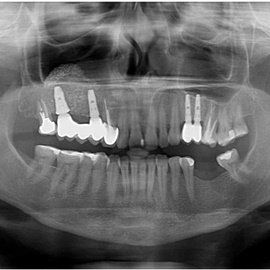

Pacjent z długą historią leczenia implantologicznego. Pierwsze implanty w pozycjach 23, 24 miał wkręcane w Warszawie przed 25 laty. Implant w pozycji górnego prawego kła ma agresywny gwint, ponieważ bezpośrednio po implantacji był obciążony (immediate loading) tymczasowym atachmentem ball abutmentv do stabilizacji tymczasowej protezy ruchomej. Kość szczęki regenerowana i odbudowywana etapami w całym górnym prawym kwadrancie. Pacjent planuje uzupełnić brakujące zęby 25, 26.